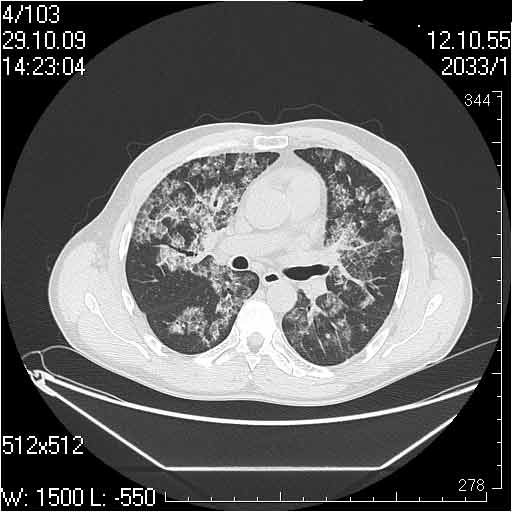

Случай №2

Мужчина 54 лет

Случай 2: картина патологических изменения довольно типична: GGOs & thickened interlobular septas = "crazy paving" sign. Наличие плотностей по типу матового стекла в сочетании с утолщением междолевых перегородок, даёт признак булыжной мостовой; на первом месте будет стоят диагноз альвеолярных протеиноз.